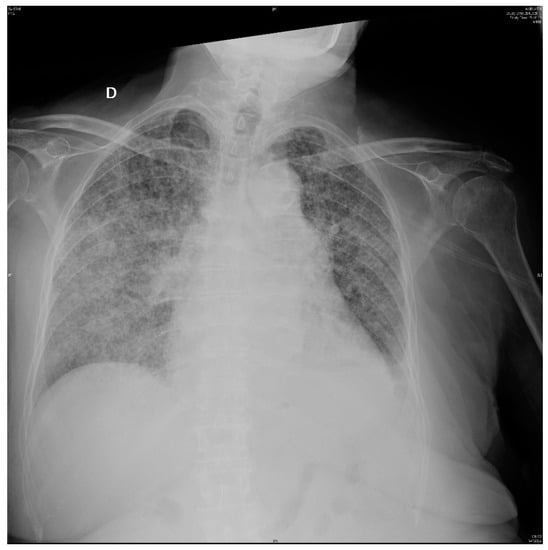

Three days later, the patient started with progressive dyspnea with productive cough. Arterial blood gas analysis showed PO2: 67 mmHg, PCO2: 39 mmHg and SatO2: 94% and a new chest X-ray (Figure 2) presented bilateral interstitial infiltrate. Sputum culture and acid-fast stain were negative. Urinary Legionella antigen was also negative.

Figure 2.

Chest X-ray on 7th day: Bilateral interstitial infiltrates.